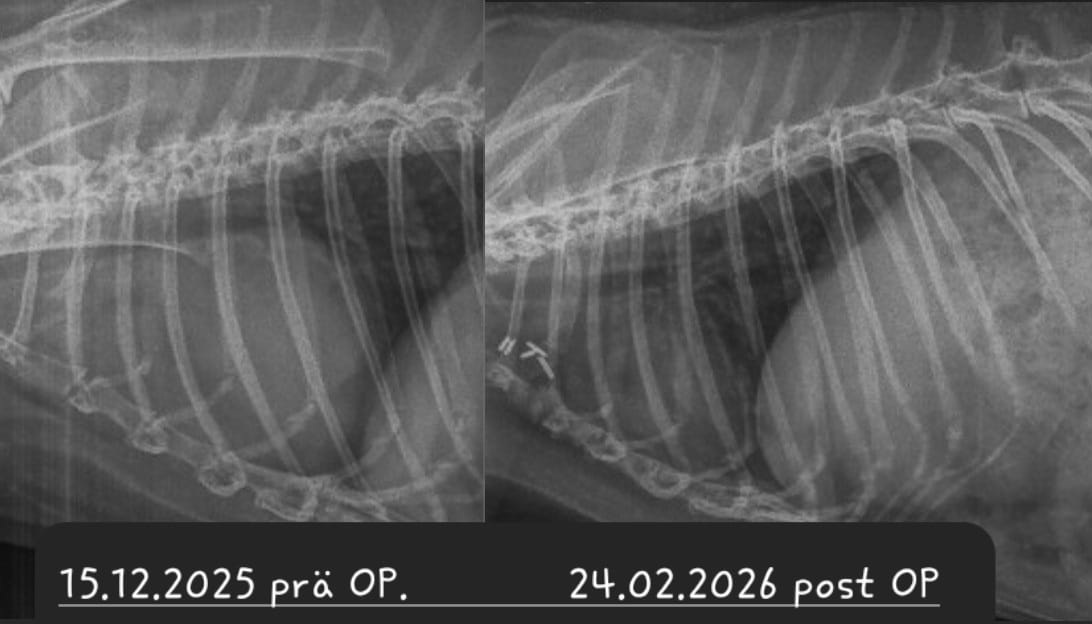

Ein Kaninchen mit Atembeschwerden oder den beschriebenen Augenveränderungen sollte zunächst geröngt werden. Hierdurch lassen sich Verschattungen im Brustkorb schnell und einfach erkennen und es muss anschließend nur noch ermittelt werden, ob es sich dabei um einen Tumor oder eine (reine) Herzerkrankung handelt. Letztere kann zu einem vergrößerten Herzen oder einem Erguss führen, was per Röntgendiagnostik nicht immer von einem Tumor zu unterscheiden ist.

• Wie sieht die Gefäßversorgung des Tumors aus? Um diese Frage zu beantworten, muss ein sogenanntes Kontrast-CT (CT nach der Injektion von Kontrastmittel) durchgeführt werden.

Bei einer Thymom- oder Lymphom-OP handelt sich um einen schwerwiegenden Eingriff, bei dem der Brustkorb des Patienten eröffnet wird und der Tumor möglichst vollständig entfernt werden muss, ohne dabei das benachbarte Herz zu schädigen. Die OP wird nur von wenigen Chirurgen angeboten. Ein Spezialist, der regelmäßig auch Patienten aus Deutschland operiert, ist Dr. Florent Modesto in Brüssel.

Sofern davon auszugehen ist, dass das Kaninchen den Eingriff übersteht und der Tumor sich vollständig entfernen lässt, ist die OP zwar die kostspieligste, aber vermutlich auch die Option mit der besten Prognose

Leider ist trotz allem damit zu rechnen, dass Zellreste des Tumors zurückbleiben und nach einiger Zeit nachwachsen. Je nach Tumor-Art ist dies allerdings mitunter erst nach 3-5 Jahren der Fall - womit das Kaninchen sehr viel Lebenszeit gewonnen hat; hinzu kommt die verbesserte Lebensqualität, nachdem die Masse aus dem Brustkorb entfernt wurde und langfristig auch keine Medikamente gegeben werden müssen.